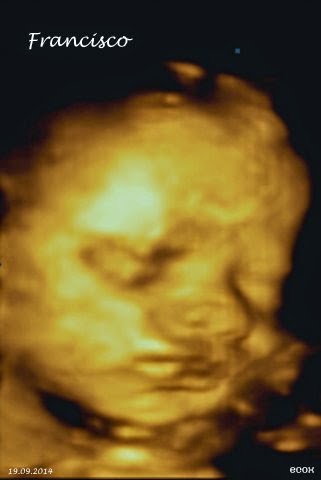

Voltei a ver o Francisco a 4D

Na sexta-feira passada, voltei ao Centro Ecox 4D Lisboa

Se bem se lembram, estive lá há mais ou menos um mês, mas como o Francisco não se deixou ver como deve de ser, voltámos a marcar uma nova data.

Lá fui eu, então, e o que é que vos posso dizer sem ser que o rapaz já revela um mau feitio tremendo e, mais uma vez, não se deixou ver em condições?

Estas foram as fotos possíveis das duas sessões :P

Nada de poder vê-lo de frente, nada de caretas, nada de chuchar no dedo… Nada!

Acontece que a carinha dele está muito "colada" à minha placenta, o que cria sombras e não o deixa ver bem. Por outro lado, o cordão umbilical anda sempre ali ao pé da carita dele e do pescoço (… e esta parte dá-me cá uma nervoseira que nem queiram saber!!!).

Mas a verdade é esta. Apesar de não ter visto o meu bebé como era esperado, esta é uma experiência mesmo muito gira. O facto de estarmos a ver, em tempo real, o que o nosso bebé está a fazer, tem uma magia indescritível! Dá ainda mais vontade de o ter cá fora (a seu tempo), tocar-lhe, senti-lo... <3

Já agora, explicar que é esta a diferença do 4D para o 3D. É que o 4D permite ver os movimentos do bebé em tempo real.

A Lídia, que é quem faz a ecografia, foi super querida e simpática. Ela transmite uma calma e uma energia super positiva.

Como o Francisco voltou a não se deixar, ver ela mostrou-se disponível para eu voltar. Não o vou fazer porque já não falta assim tanto, mas gostei da disponibilidade e simpatia :)

Resumindo, recomendo a experiência a todas as futuras-mamãs!